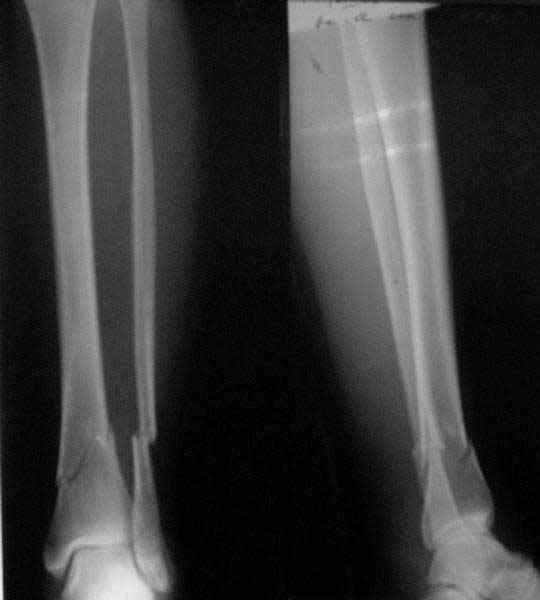

Направили к нам пациентку 35 лет с переломом дистального отдела костей голени.

У нас сделали снимок сзахватом обоих суставов - еще и проксимальный метафиз сломан. Чем бы у вас фиксировали такой перелом? Как его правильно закодировать по классификации АО?

Можно либо как два перелома - 41A+42B. А можно как один сегментарный 42С.

41.A2.1 for a proximal fracture

42.B1.3 for a distal fracture

Is very difficult take an exactly AO/OTA group for a good classification Probably the locked IM nail is a good option.